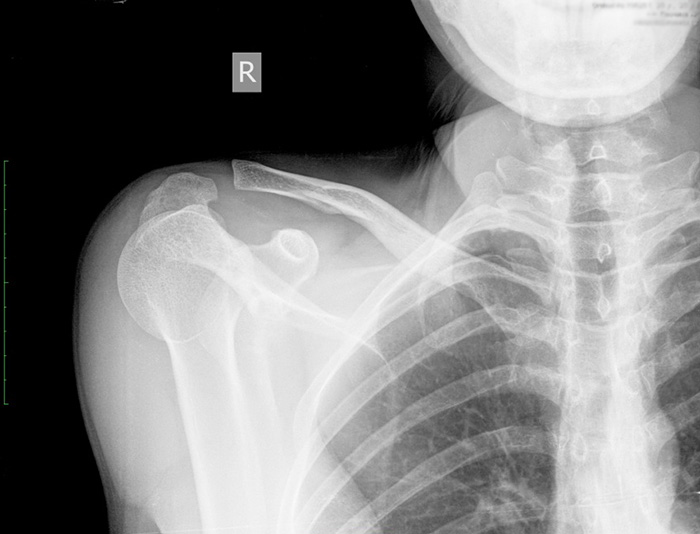

Переломы ключицы

Симптомы перелома сложно спутать с чем-то другим, ведь появляются они преимущественно после травм, о которых пациент помнит: удары, толчки, падения на выпрямленные руки или локти. Боль при переломах очень сильная, отечная, появляются синяки, кость может сменить привычное положение.

Вывихи и смещения

Вывих плечевого конца ключицы сопровождается острой болью

Грудинный конец ключицы, которым она крепится к клетке, может произойти из-за травм и падений, а также после ударов. Встречается патология редко и сопровождается такими симптомами:

- сильным отеком;

- выпячиванием ключицы или западанием;

- болью и покраснением.

Другой конец, акромиальный, имеет несколько связок, которыми крепится к лопаткам. Если они рвутся, пациент испытывает острую боль, возможность повернуть плечом резко ограничивается.

Повреждения акромиально-ключичного сустава

Этот структурный элемент находится в области лопатки и ключицы, где они пересекаются. Появляется травма преимущественно после удара или падения. Вызывает сильную боль, отечность, повышенную чувствительность области, выступы и смещения кости. Избавиться от травмы можно оперативным путем или с помощью плечевой скобы для стабилизации.